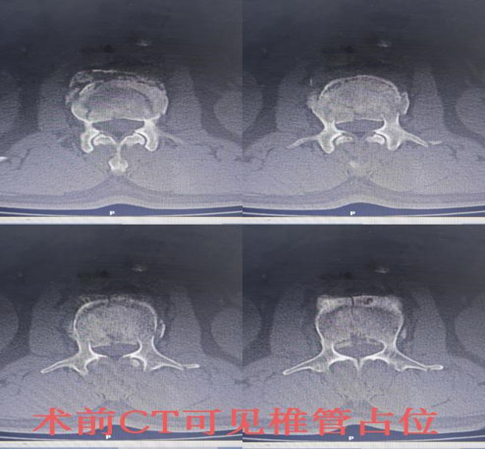

患者李某某,男,59岁,系“摔伤致腰背部疼痛伴活动受限2小时余”入院;入院后予以完善相关检查,CT示:腰2椎体爆裂性骨折,侵占部分椎管,L2左侧横突骨折。MRI提示:L2椎体压缩性骨折,L2右侧椎板骨折;腰椎退行性变;L2/3、L5/S1椎间盘突出。摄片提示:L2椎体楔形改变,椎体前缘压缩1/3。

骨伤一科陈孝贵主任指出:根据患者病史、体征及影像学表现,患者腰椎压缩性骨折(L2 爆裂性)诊断明确,对于脊柱骨折保守治疗患者,需要长期卧床,极易出现褥疮、坠积性肺炎、下肢静脉血栓形成、肺栓赛等并发症,保守治疗椎高丢失会引起腰椎后凸畸形、慢性腰疼及继发腰椎不稳等后遗症,对于该患者,手术指针明确,手术目的:恢复椎高及清理椎管占位,促进早期下地,减少并发症及远期后遗症。建议患者行微创手术治疗方案-经皮椎弓根螺钉复位内固定术,患者及其家属同意并积极配合治疗方案,积极术前准备,在排除手术禁忌后,陈主任为其行手术治疗,手术顺利,术后2天即可佩戴支具下床活动。